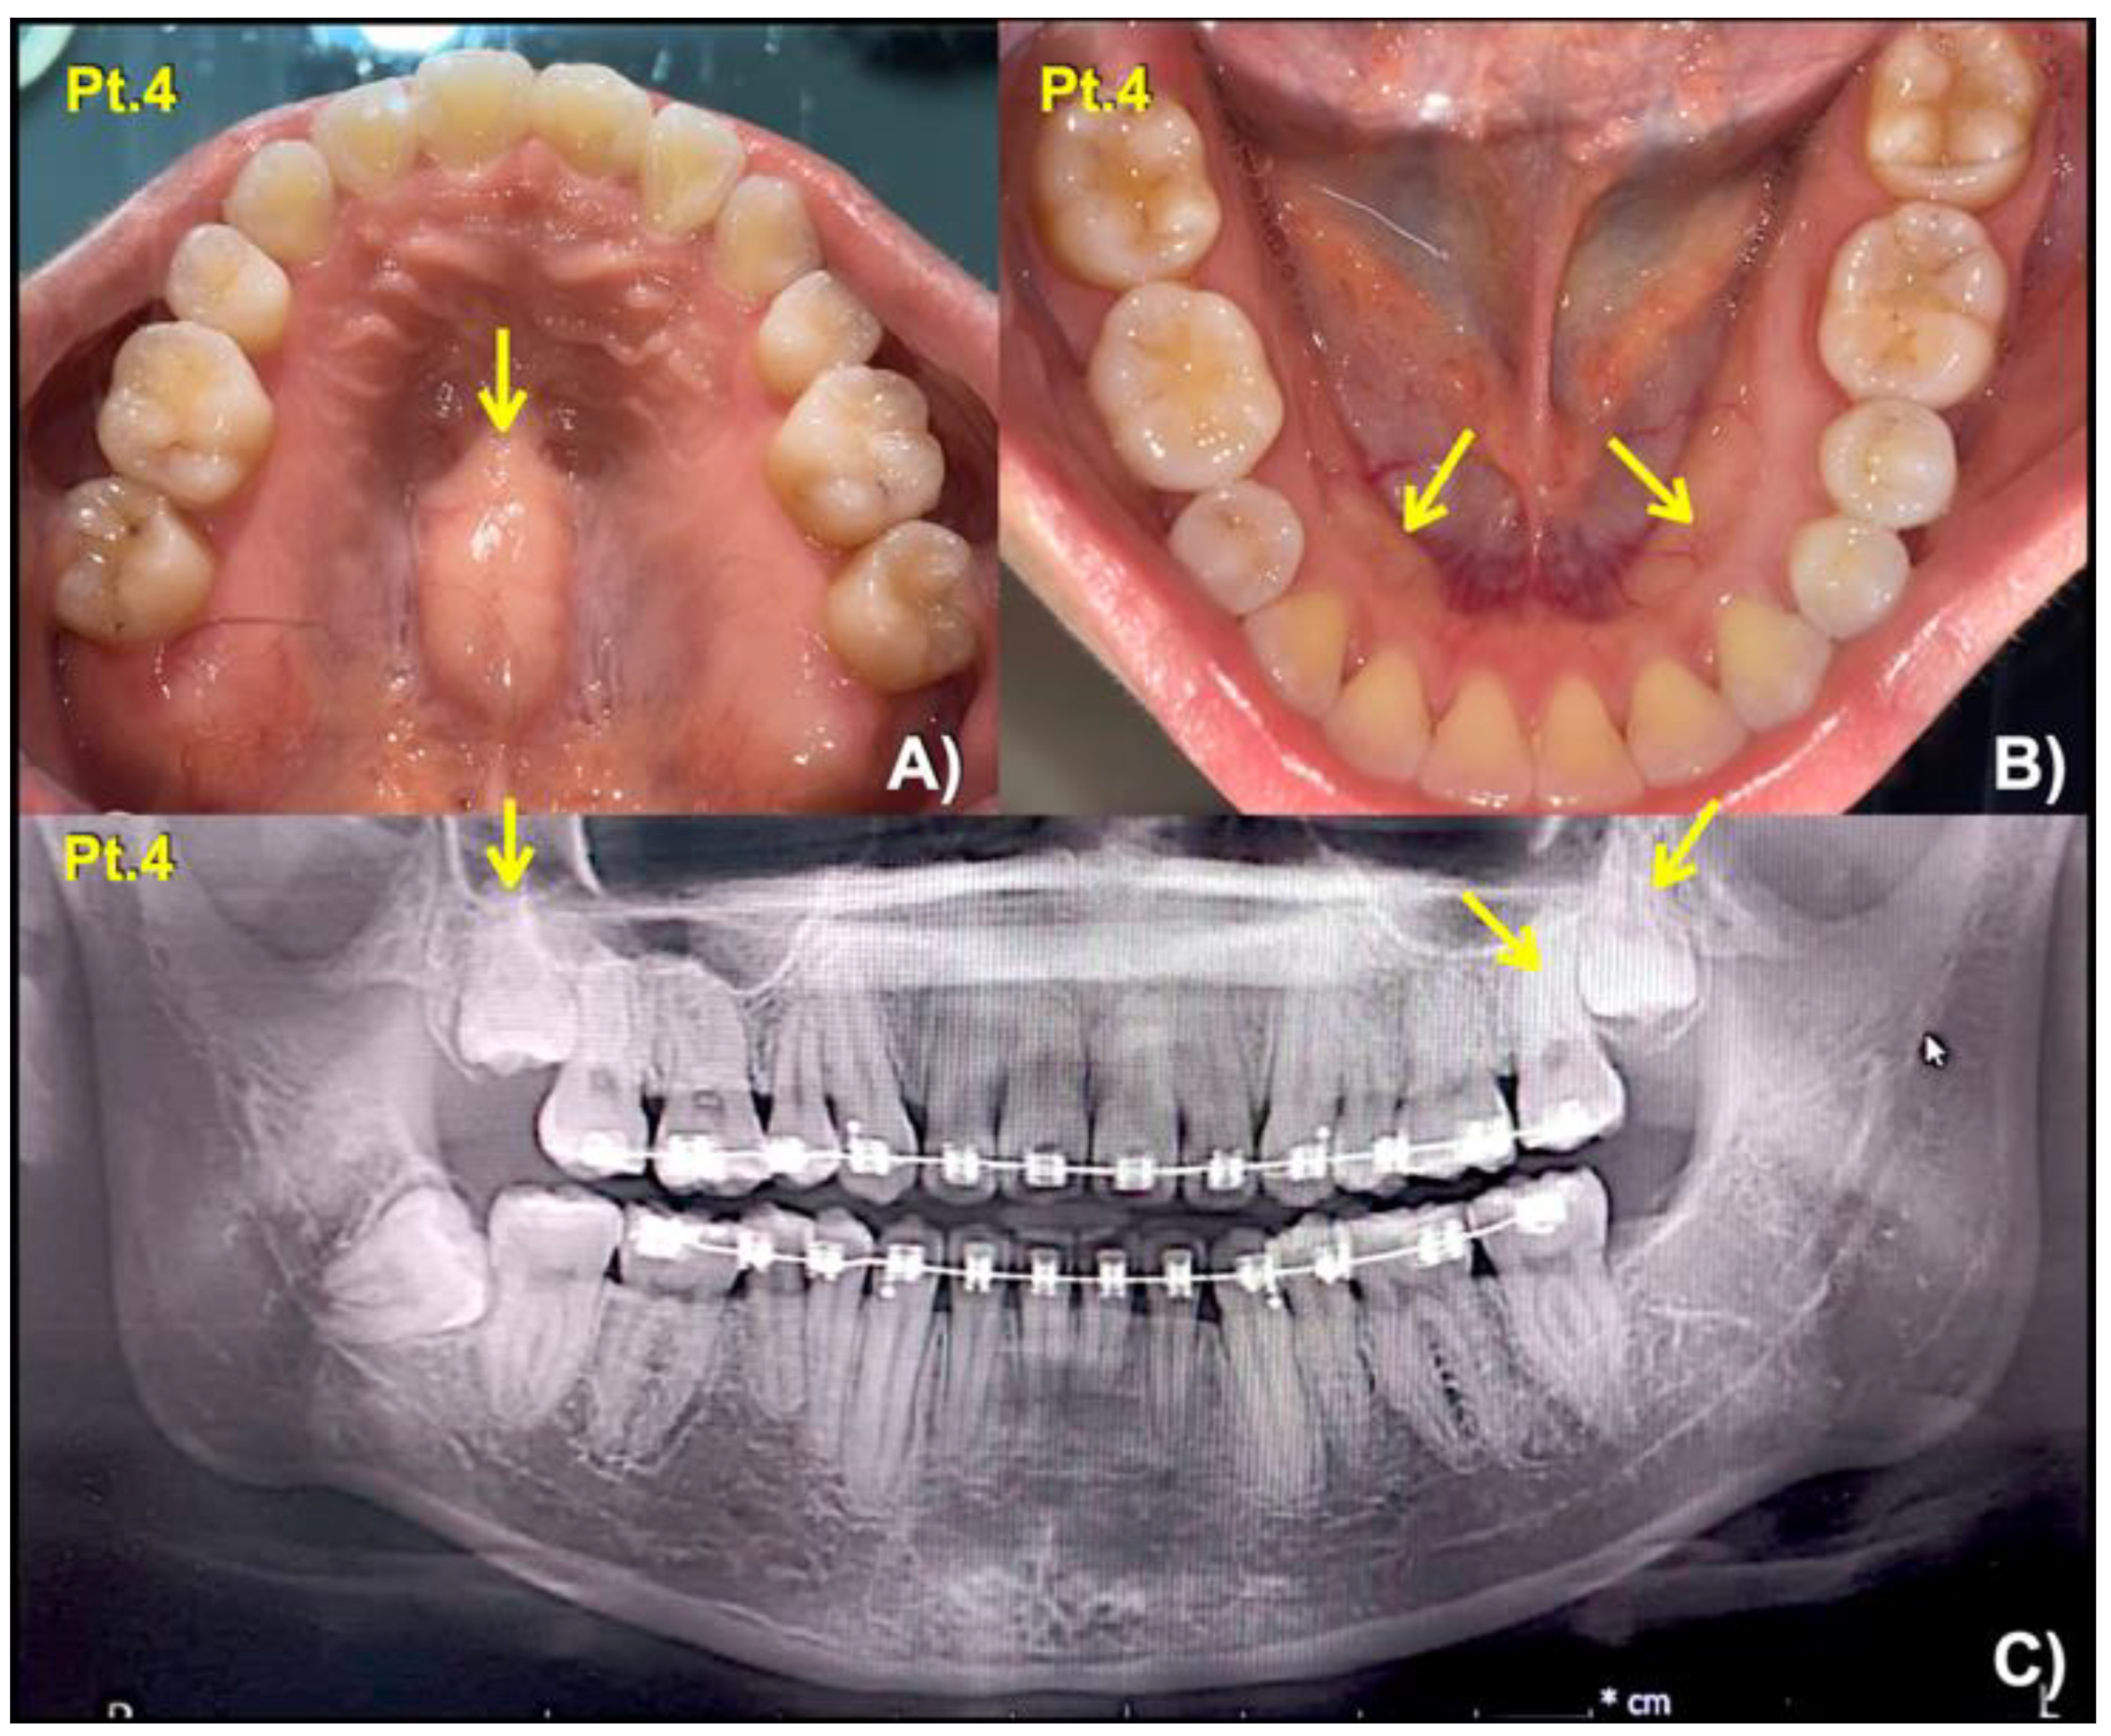

| 4 (Female: 30 Yr) | 2 | Mesiodens (Conical; unerupted) long roots of mandibular canines, short roots of second premolars, unseparated roots of second and third molars, torus mandibularis, and torus palatinus | c.3940G > A; p.Gly1314Ser chr11: g.46896640 C > T rs371961330 MAF = 0.00009579 | 0.9966 (pathogenic) | 18.11 |